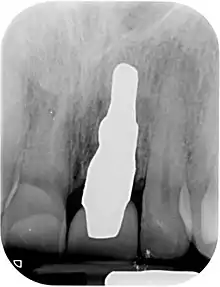

A new attempt was made by Pirker et al 2004 in a human trial with root analogue zirconia implants, but this time by applying differentiated osseoingration on the surface. In 2011 he reported 90% success rate with this method in a 2.5 year human trial.[11]

Mangano et al in Italy in 2012 reported the successful clinical use of a custom-made root analogue implant made by direct laser metal forming (DLMF) from a CBCT scan. This demonstrated that it is possible to combine CBCT 3D data and CAD/CAM technology to manufacture root-analogue implants with sufficient precision.[24]

- ↑ Pirker, W; Kocher, A (2008). "Immediate, non-submerged, root-analogue zirconia implant in single tooth replacement". International Journal of Oral and Maxillofacial Surgery. 37 (3): 293–5. doi:10.1016/j.ijom.2007.11.008. PMID 18272340.

- ↑ Pirker, W; Kocher, A (2009). "Immediate, non-submerged, root-analogue zirconia implants placed into single-rooted extraction sockets: 2-year follow-up of a clinical study". International Journal of Oral and Maxillofacial Surgery. 38 (11): 1127–32. doi:10.1016/j.ijom.2009.07.008. PMID 19665354.

- 1 2 3 Pirker, W; Wiedemann, D; Lidauer, A; Kocher, A (2011). "Immediate, single stage, truly anatomic zirconia implant in lower molar replacement: a case report with 2.5 years follow-up". International Journal of Oral and Maxillofacial Surgery. 40 (2): 212–6. doi:10.1016/j.ijom.2010.08.003. PMID 20833511.